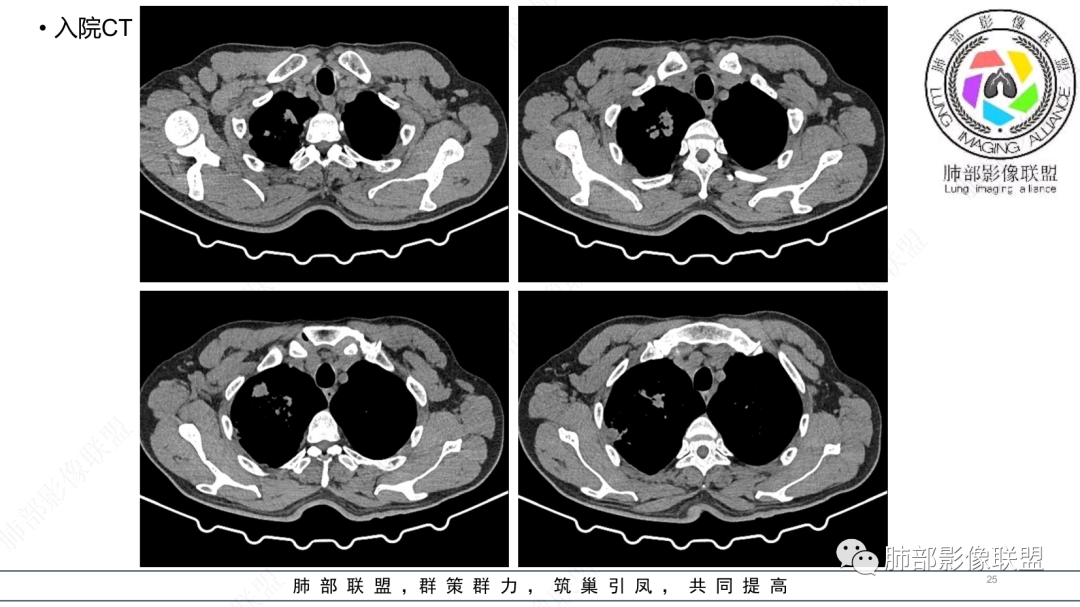

中年男性,急性病程,发热,炎症指标明显增高;环卫工人。

CT:双肺延支气管血管束分布斑片状、团块状、树芽状密度增高影,部分边界模糊,支气管扩张、部分管壁增厚。考虑气道吸入细菌性感染,铜绿假单孢?